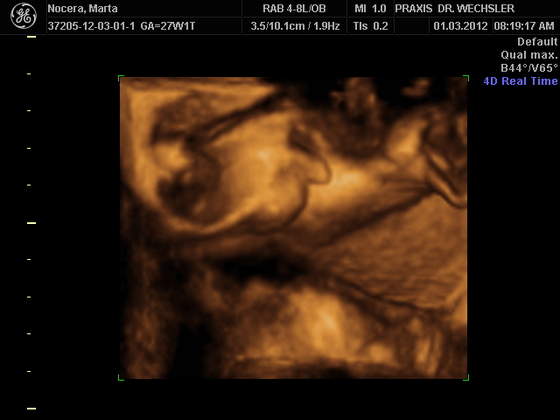

Karwiczki BBOOSSKKIEE ZDJĘCIA !!!!!!!!! ŚLICZNE MALEŃSTWO !!!!!

Aniu u nas tez calkiem wyraznie nie wyszly te zdjecia,nawet lekarz nie byl za bardzo zadowolony,ale fajnie,ze choc takie mamy,kosztowalo to nie malo bo 90 euro,maz twierdzi,ze duzo za drogo i spodziewal sie czegos lepszego,hmmm

za 3 miesiace bedzie lepiej widzial

nagranie mamy na dvd i do tego zdjecia 48 sztuk.